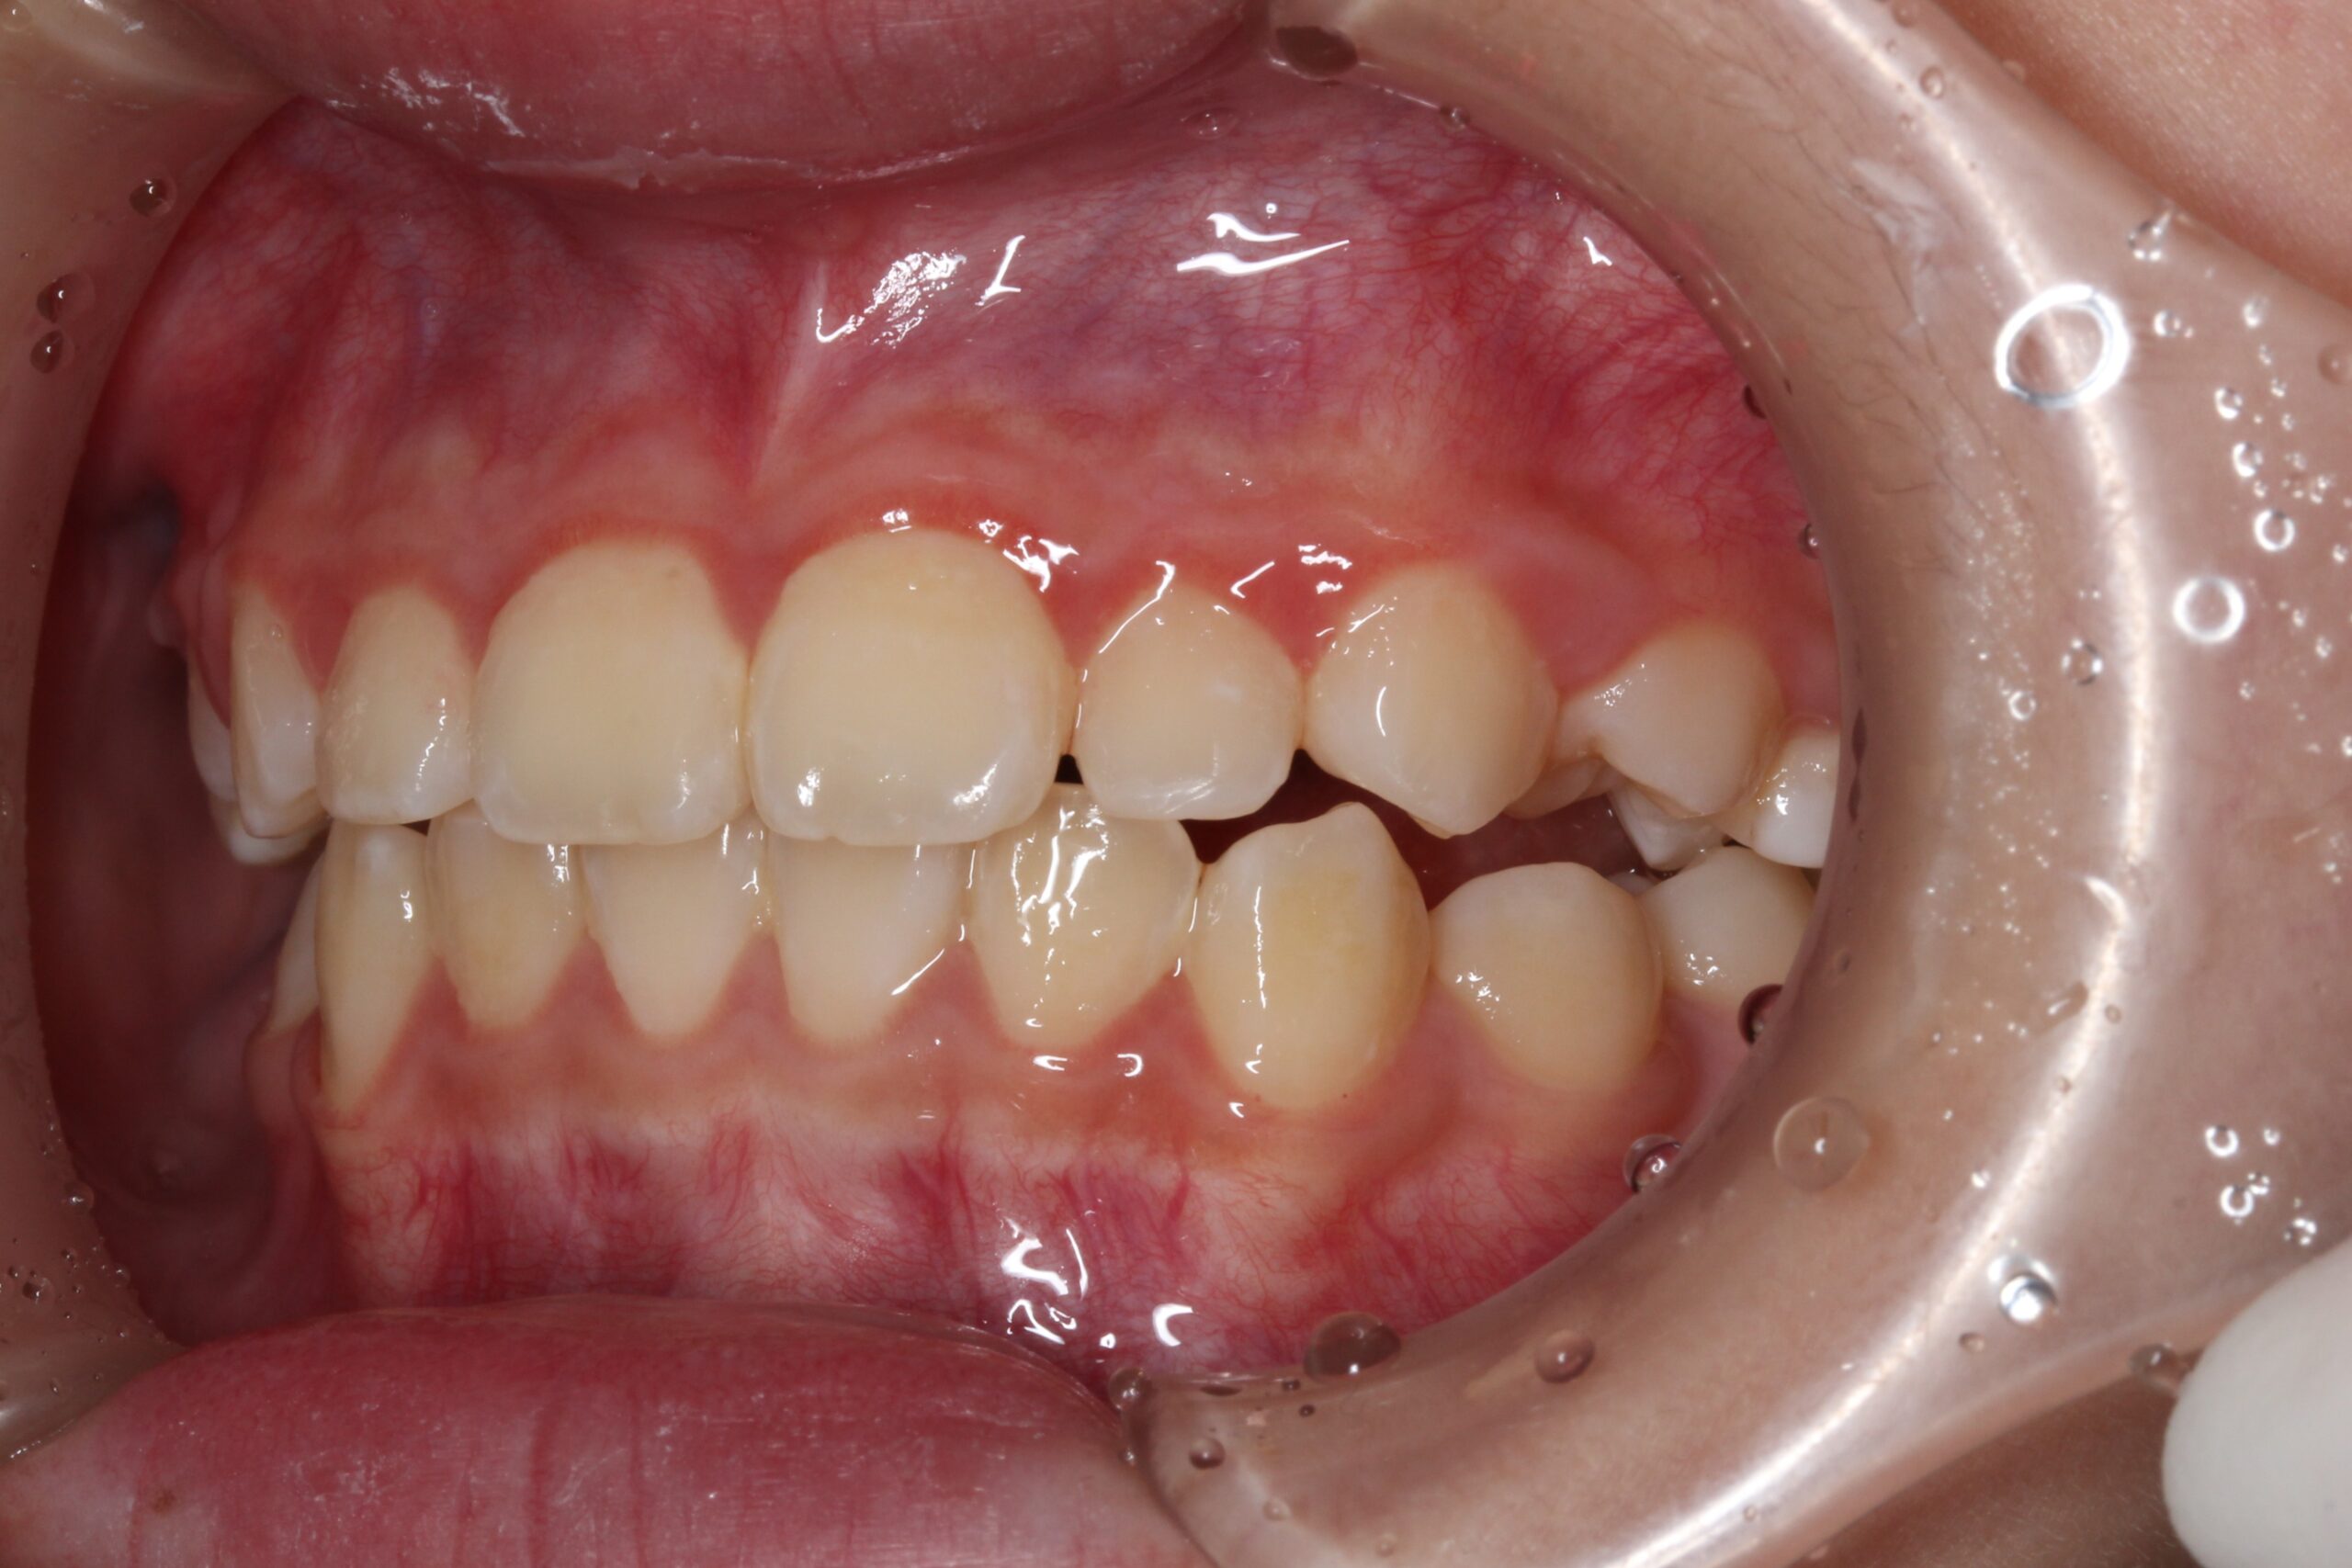

矯正術前:左側

矯正術後:左側